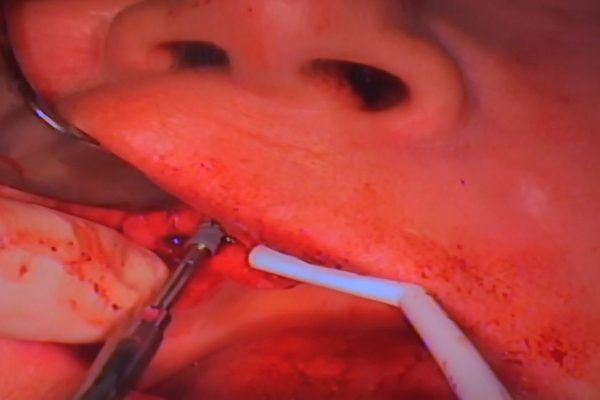

W ostatni weekend czerwca 2018 roku kursanci II Sezonu Preludium Implantologii odbyli piątą, finałową sesję, która w całości podporządkowana była praktyce. W ciągu dwóch dni zabiegowych Lekarze uczestniczący w szkoleniu przeprowadzili szereg zabiegów pod kierunkiem dr n.med. Violetty Szycik. Wszczepili 17 implantów oraz przeprowadzili ekstrakcje i zabiegi regeneracyjne kości. Zabiegi były wykonywane także w sedacji dożylnej z udziałem specjalisty anestezjologii i intensywnej terapii dr Jolanty Grzybowskiej. Preludium implantologii to nowy program edukacyjny dla adeptów implantologii stomatologicznej, którego celem jest wprowadzenie do implantologii poprzez pozyskanie wiedzy w szerokim zakresie i uwzględnieniem szczegółów mających decydujące znaczenie dla powodzenia leczenia implantologicznego. Ale tak jak wszystkie szkolenia w Instytucie Vivadental, w tym wiodące Practiculum Implantologii, zorientowane jest na praktyce i samodzielnym wykonywaniu zabiegów pod kierunkiem Mentora. To najlepsza edukacja w medycynie zabiegowej, a zarazem najlepszy start do implantologii.